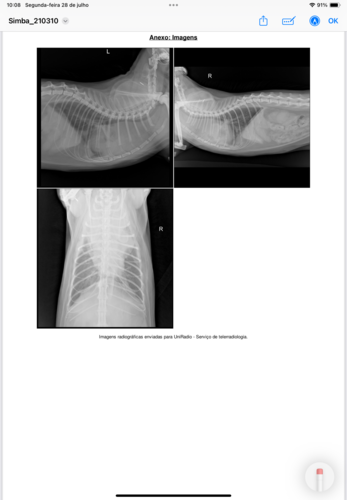

Há algumas semanas, eu comecei a passar muito mal… Estava com dificuldade pra respirar, muito quietinho e sem forças. A mamãe Nayla e o papai Rafa ficaram super preocupados comigo. Num final de semana, tudo piorou de vez, e eu tive que ser levado às pressas para o hospital veterinário.Fiquei internado por alguns dias, recebendo medicação, oxigênio e muitos cuidados. Foi nesse momento que, após um raio-X, veio uma notícia que assustou todo mundo: fui diagnosticado com uma neoplasia mediastinal, um tipo de tumor que fica entre os pulmões e o coração. 😔Além disso, sou um gatinho positivo para FeLV (Leucemia Felina), o que torna meu sistema imunológico mais frágil e o tratamento ainda mais delicado. Mas mesmo com esse diagnóstico difícil, a mamãe e o papai nunca deixaram de lutar por mim, eles me acompanham em cada consulta, me dão amor, carinho e toda força que eu preciso pra continuar.Depois do diagnóstico, passei por uma veterinária oncologista, e agora estou começando meu tratamento com medicações oncológicas e sessões de quimioterapia. A boa notícia é que estou reagindo bem! Estou comendo, me limpando, ronronando e mostrando que ainda tenho muita vontade de viver. 🧡Mas esse tratamento tem um custo alto, e por isso estamos aqui pedindo, com muito carinho: você pode nos ajudar nessa luta?Qualquer valor, mesmo pequeno, vai fazer uma diferença enorme no meu tratamento — ajudando a cobrir consultas, exames, internações, medicações e quimioterapia. E se você não puder ajudar com dinheiro, tudo bem! Só de compartilhar minha história, você já estará nos dando uma força enorme. 🙏Sou um guerreirinho, e com a ajuda de vocês, quero continuar vivendo com qualidade, sentindo o amor do meu papai e da minha mamãe, e enchendo a casa com meus ronronados e olhares carinhosos. 💛